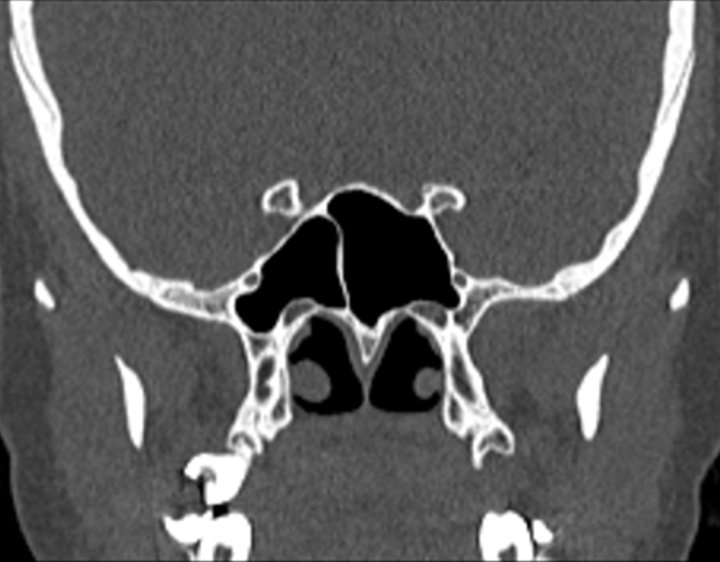

Click any image for labels.